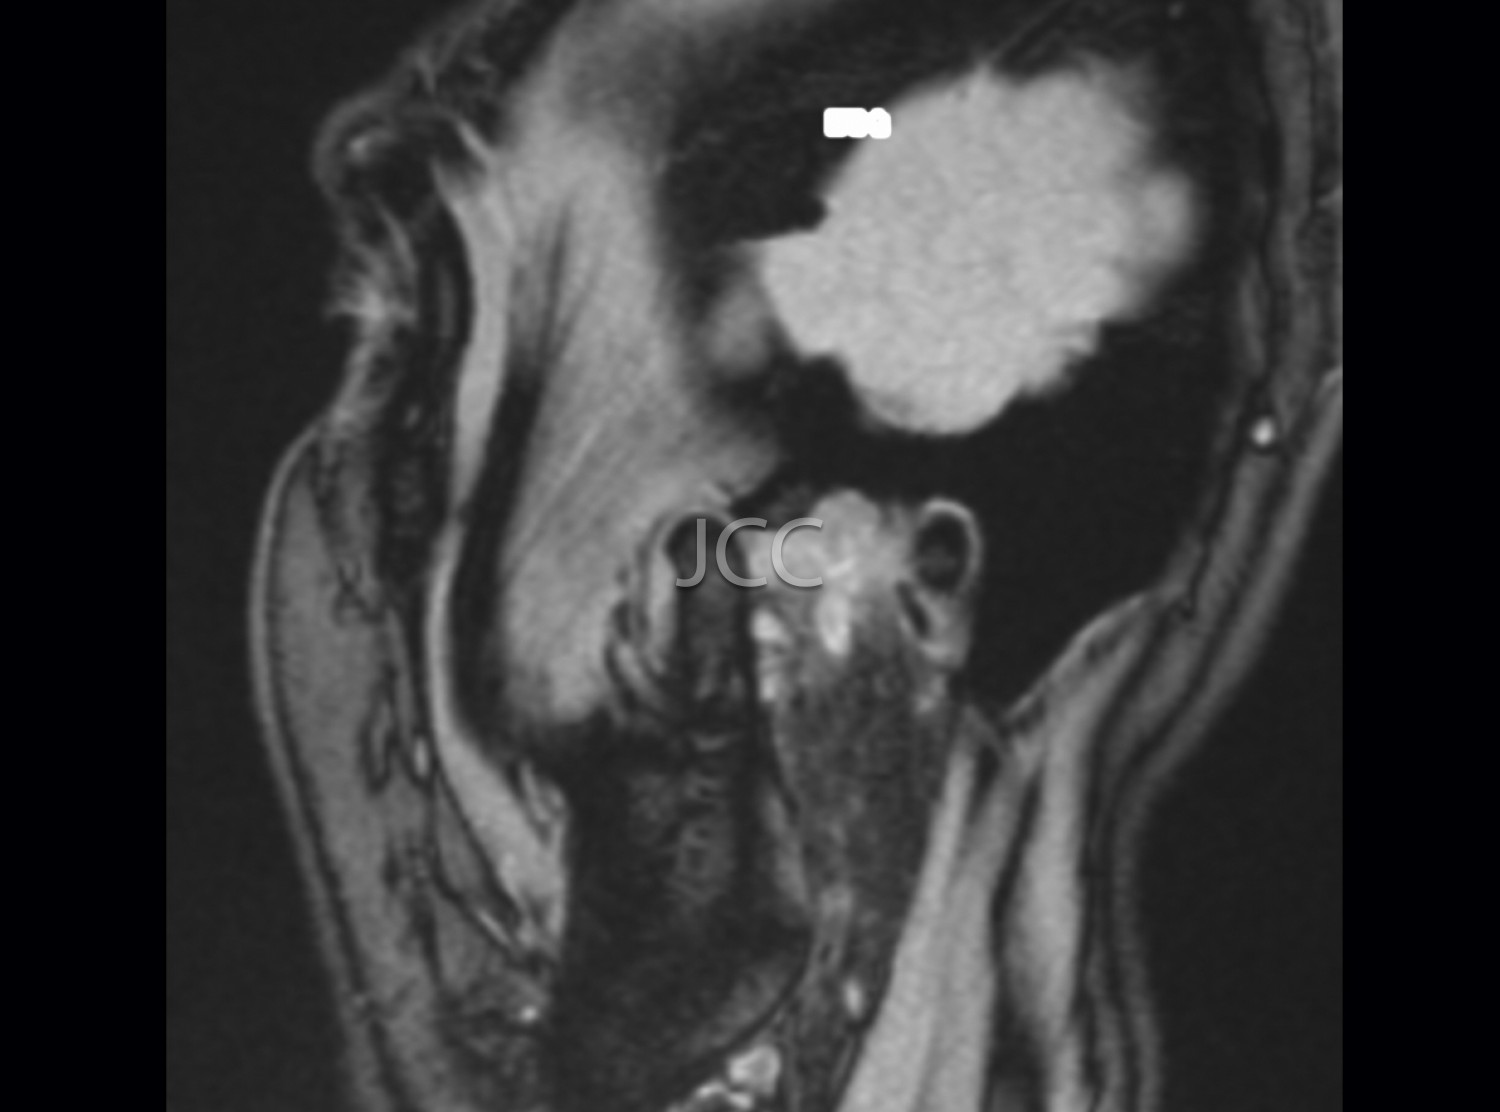

MRI is currently the first-line examination for the study of TMJs pathology. They allow the dynamic study of the relationship of the articular disc and mandibular condyle in the various degrees of buccal opening.